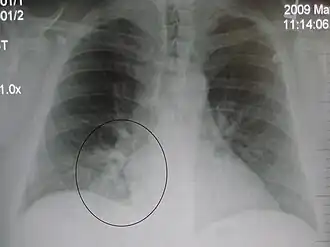

AP CXR showing left lower lobe pneumonia associated with a small left sided pleural effusion -